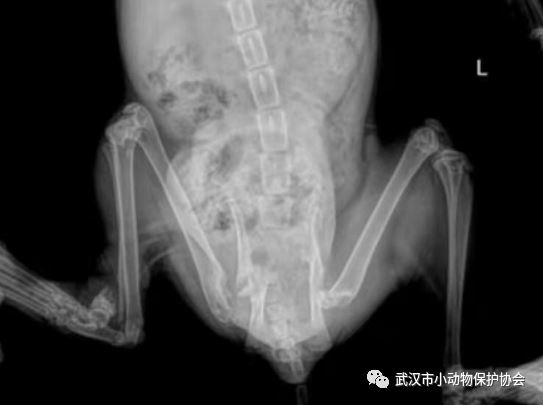

经过检查,猫咪不仅是膀胱问题,右后腿的股骨头粉碎性骨折,医生通过两次手术,分别修复了膀胱和截肢,绝育手术也安排了。